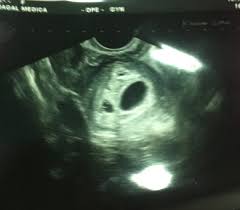

10 a 13 semanas e meia de gestação. Com 5 semanas de gestação o saco gestacional mede em torno de 4 a 16 mm e pode dobrar de tamanho ao decorrer da semana. O seu corpo A complexidade inicial do desenvolvimento humano faz com que as primeiras semanas de gestação sejam as mais críticas da gravidez.

Nesta semana ocorre uma gloriosa explosão de força. Veja o desenvolvimento do bebê com 5 semanas de gravidez. 1 Normalmente quando é feito o ultrassom com 5 semanas o desespero é consequência já que dificilmente conseguirá ver algo. Com a finalização do desenvolvimento das principiais estruturas e órgãos vitais do bebé por volta da 13ª semana o risco de aborto diminui para cerca de 65. Nesse momento os hormônios estão fervendo transformando o humor da mulher em uma montanha-russa. O coração está se dividindo em câmaras e logo assumirá um ritmo mais regular. Ao final desta semana ele terá o tamanho de um feijãozinho. Algumas mulheres não percebem que a menstruação atrasou pois em alguns casos quando o zigoto se implanta no útero nidação ocorre um pequeno sangramento e assim elas pensam que. 5º mês de gestação Biologia O quinto mês de gestação compreende da 17ª à 20ª semana lunar.

Sua cabeça e seu coração são tão pequenos que um ultrassom nesta fase seria impossível de detectar. O seu coração bate pela primeira vez e a um ritmo duas vezes mais rápido do que o da mãe. Com 5 semanas de gestação o saco gestacional mede em torno de 4 a 16 mm e pode dobrar de tamanho ao decorrer da semana. 5 Semanas de gestação. Minha primeira gestação - 5 semanas About Press Copyright Contact us Creators Advertise Developers Terms Privacy Policy Safety How YouTube works Test new features 2020 Google LLC. 5 Semanas de Gravidez Do 29º dia ao 35º dia de gravidez. Desenvolvimento do bebê - 5 semanas de gestação Desenvolvimento do bebê.